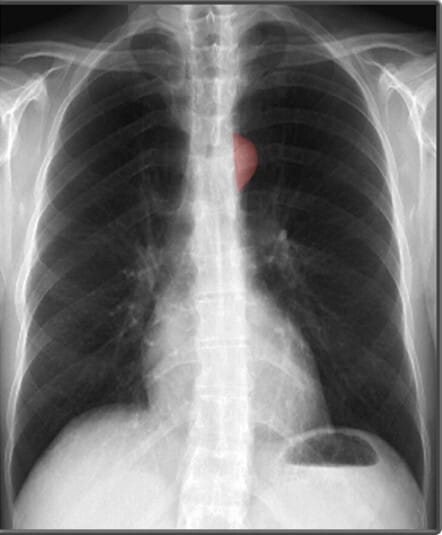

종격동(mediastinum)은 심장과 주요 혈관, 기관(trachea) 등이 위치하는 공간으로, 이들의 크기와 모양을 분석하는 것이 중요합니다.

| 대동맥궁 (Aortic Arch) |

| ✅ 좌측 폐문(hilus) 위에서 둥글게 보이며, 확장되거나 비대해지면 대동맥류 또는 고혈압성 변화 가능성을 고려해야 합니다. |

| 기관 (Trachea) |

| ✅ 정중앙에 위치해야 하며, 편위되어 있다면 종격동 이동(예: 무기폐, 기흉)을 의심해야 합니다. |